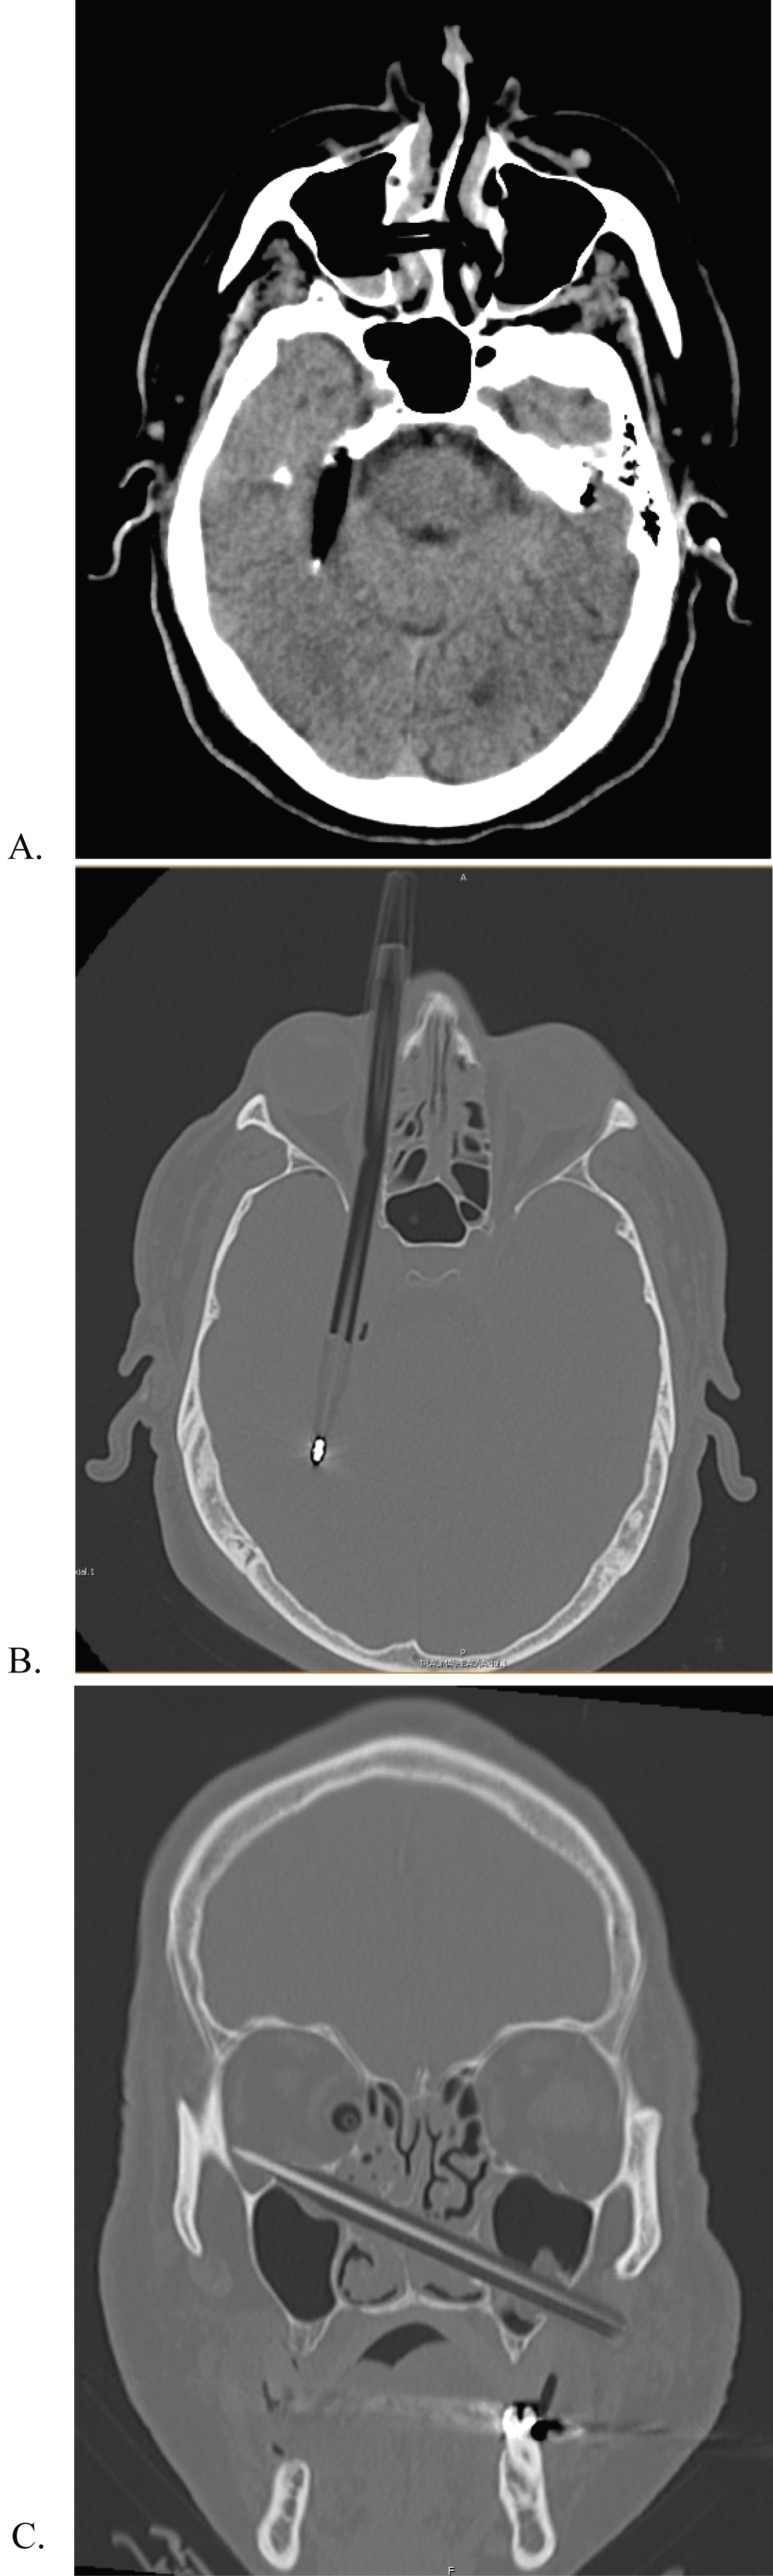

A 53-year-old male inmate sustained a transorbital penetrating injury with a ballpoint pen, and a transmaxillary penetrating wound injury with a pencil. He was transferred to our university hospital fully alert, with stable vital signs, and GCS score of 13 (E3, V4, M6). On presentation, only the pen cap was visible, extending outward from his right medial canthal fold (Figure 1). Physical exam demonstrated right sided ophthalmoplegia, with absent pupillary responses to both direct and consensual light, and loss of light perception in the right eye. Left sided extraocular movements remained intact, and the left pupil was reactive to direct but not consensual light. His neurological exam was otherwise, normal. A computed tomography angiography (CTA) scan of the head demonstrated the pen entering the right medial orbit, extending intracranially through the superior orbital fissure along the lateral wall of the right cavernous sinus, and terminating supratentorially in the right temporal lobe (Figure 2A and Figure 2B). There was no evidence of hemorrhage along the track, and the right internal carotid artery was separated from the pen by two millimeters. A second tubular foreign body was seen beginning at the anterior aspect of the left masseter muscle, entering the lateral wall of the left maxillary sinus, and then passing through the medial wall of the sinus, inferior turbinate, nasal septum, and right ostiomeatal complex before terminating in the inferolateral right orbital wall (Figure 2C).

Figure 2: (A,B,C) Brain and Bone window axial and coronal CT scans demonstrating ball point pen and pencil trajectory. View Figure 2